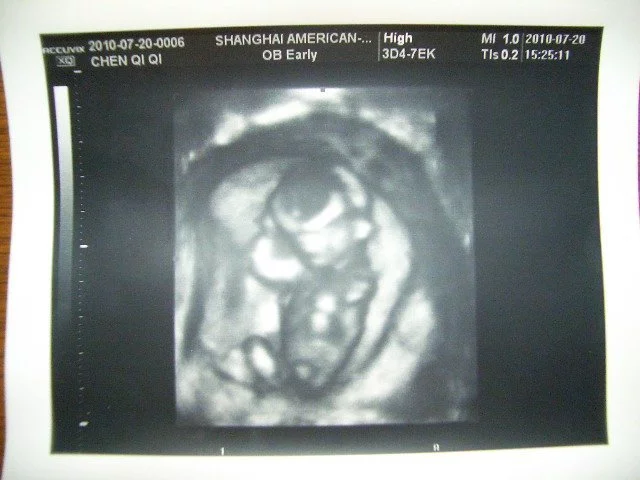

顶臀径:又称头臀长(crown-rump l食天ength 简写CRL),指胎儿从颅顶顶部到臀部外缘的距离,一般怀孕7-12周左右测量。

顶臀径:又称头臀长(目鲁式行crown-rump length 简写CRL),指胎儿从颅顶顶部到臀部外缘的距广离,一般怀孕7-12周左右测量。

超声检查早孕胎儿时,常用顶臀径估测胎儿的孕龄,此为最为准确的估测方法。6周初由于胚芽太小,测量不准来自确,随着孕周的增大,胚胎的生长,其形态曲线为C形,头端相对较大而棉容易辨认。故此采用以下公式计算妊娠龄。

公式: 妊娠龄(周)=CRL(cm)确品用且放朝九境科+6.5

测量标准切面:取胎体或躯干最长,最直的正中矢状面切面图像。